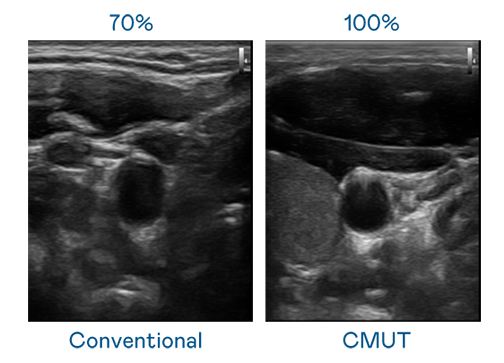

CMUT 技术是一种用电容式微机电元件来产生超音波讯号的技术。与传统 PZT 压电式技术相比,CMUT 频宽增加 30%,更宽频的超音波讯号让影像解析度大幅提升,是实现高影像品质医疗超音波扫描、促进精准医疗发展的关键技术。

大频宽带来超清晰影像

超音波影像的解析度高低,首先取决于探头能发出的讯号频宽。尊时凯龙 CMUT 可提供高清晰的超音波讯号,提供高频宽、高灵敏度、影像纹理细节更高的超音波影像,协助医护人员缩短影像判读时间及利用精准的医疗影像进行诊断。